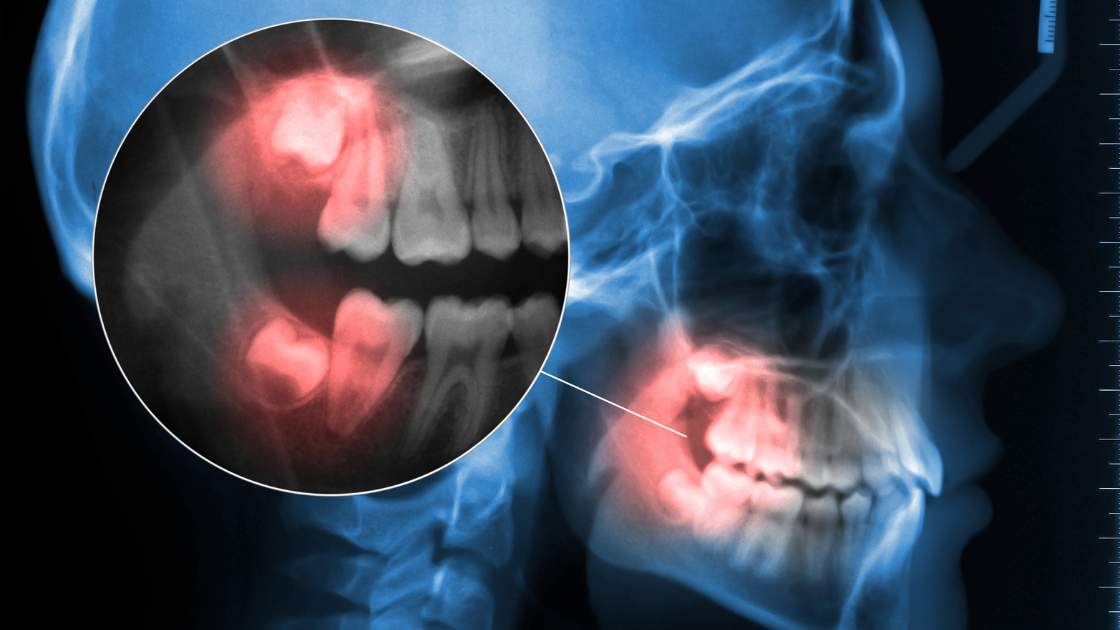

Wisdom teeth, also called third molars, are the last  teeth to erupt in the mouth, usually in the late teens or early 20s. There are some important things to know about wisdom teeth. Not everyone has:Some people have no wisdom teeth at all, while others have 1, 2, 3, or 4 wisdom teeth.They can cause problems:Wisdom teeth can cause problems if they don’t have enough space in the mouth  to grow  properly.

and can lead to  damage to adjacent teeth.You may need to remove:If  wisdom teeth are causing problems, your dentist may recommend removing them. This is a common procedure and is usually done under local anesthesia or sedation.Recovery time:Recovery time after wisdom tooth extraction varies, but usually takes about a week. Swelling, pain, and bleeding may occur for a few days after the procedure, but it will gradually improve.